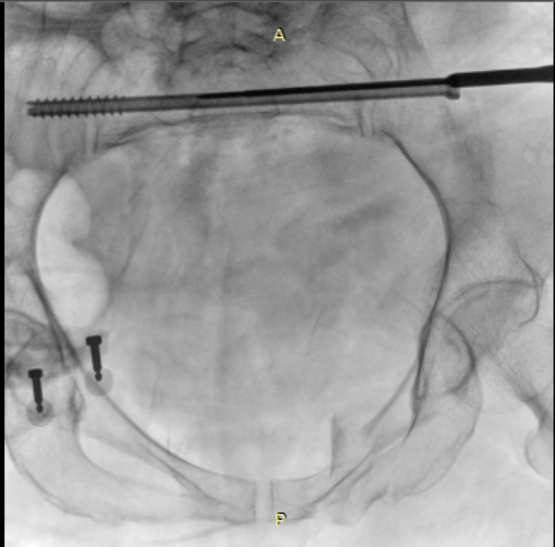

术中使用骨科手术机器人导航定位置入骶髂螺钉

术中透视见骶1骶2两枚骶髂螺钉位置满意